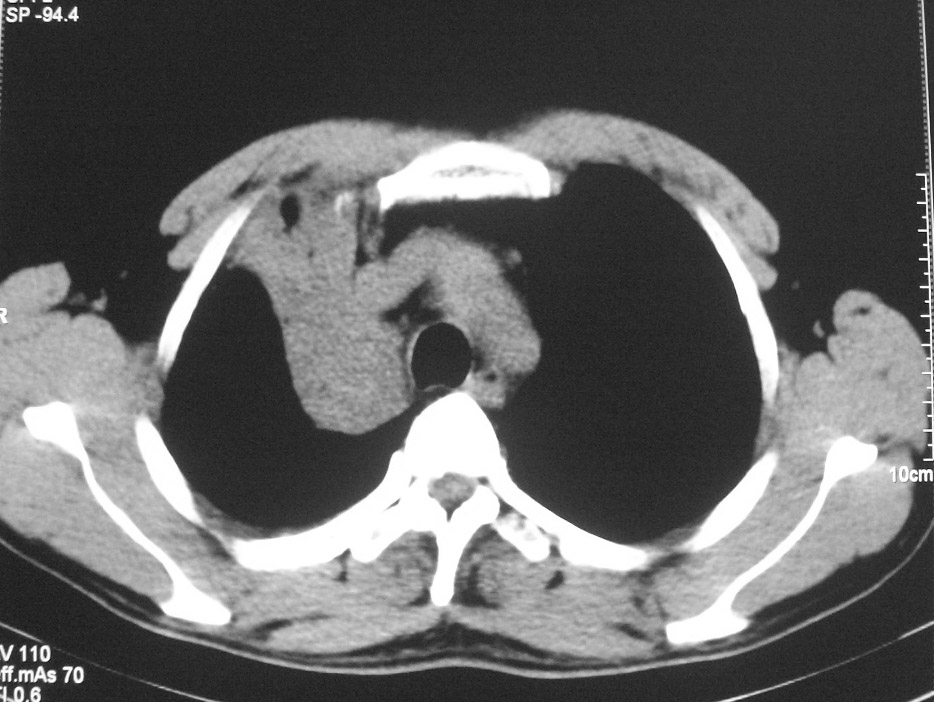

标题: CT5485:[原创]肺部占位请讨论

右肺上叶中央型肺癌并上叶肺不张、纵隔淋巴结肿大

右肺上叶中央型肺癌并上叶肺不张

右肺上叶中央型肺癌并上叶肺不张。

右肺上叶支气管后壁增厚,呈鼠尾状狭窄,纵隔内未见明显增大的淋巴结影,考虑为中央型肺癌伴右上肺不张

中央型肺癌伴肺不张

右肺上叶中央型肺癌并阻塞性炎症、阻塞性肺不张……